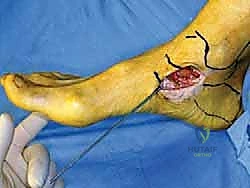

الخطوة الثالثة: الشق الجراحي والوصول الآمن

يتم عمل شق جراحي دقيق ومدروس على الجانب الداخلي للكاحل، خلف وتحت الكعب الإنسي. يستخدم الدكتور هطيف تقنيات تشريحية دقيقة لحماية الهياكل الحيوية المحيطة، وخاصة العصب الصافن (Saphenous Nerve) والوريد المرافق له، لتجنب أي تنميل أو ألم عصبي مزمن بعد الجراحة.